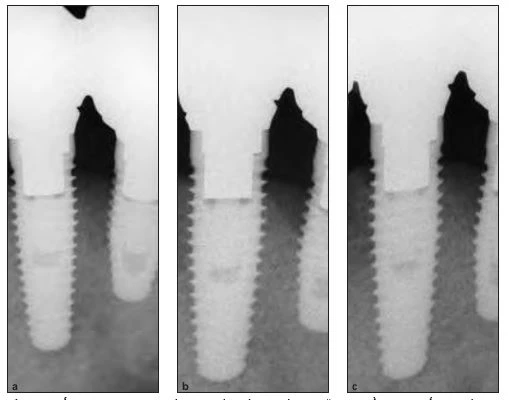

Hình 1a to 1c (a và b). Hình ảnh hiển vi điện tử tương phản pha. Lớp TiUnite được loại bỏ hoàn toàn bởi những bọt nổ vi thể. Bề mặt mới lộ ra không hề bị tan chảy hay biến dạng bởi hiệu ứng làm nóng của việc chiếu laser. Phần bên trái và bên trên thể hiện bề mặt trước khi chiếu laser Er:YAG, trong khi đóphần bên phải và phía dưới thể hiện bề mặt sau khi chiếu laser Er:YAG. (c) Implant với điều trị laser ở phần chóp.

Tại 50mJ/mm2, lớp TiUnite không thể được loại bỏ hoàn toàn.Tại 100 mJ/mm2, lớp TiUnite bằng phẳngcũng được loại bỏ hiệu quả, và bề mặt lộ ra cũng không bị biến dạng do nóng chảy, do cacbon hóa, hay do những tác động khác của nhiệt (Hình 1). Tại 200 mJ/mm2, lớp TiUnite và cả lớp titan bên dưới bị nóng chảy.

Hình 3a đến 3c cho thấy implant sau 2 tuần ở độ phóng đại 10× và 200×. Sự xâm nhập nhẹ của mô dạng xương được ghi nhận trên cả bề mặt không chiếu laser (Hình 3b) và bề mặt chiếu laser (Hình 3c). Hình 4a đến 4c cho thấy implant sau 4 tuần ở độ phóng đại 10× và 200×

Mô dạng xương được hình thành trên bề mặt không chiếu laser (Hình 4b), và mô dạng xương cũng hình thành dọc bề mặt implant chiếu laser và lấp đầy một phần ba khoảng trống (Hình 4c). Hình 5a đến 5c cho thấy implant sau 6 tuần ở độ phóng đại 10× và 200×. Xương hình thành được thấy trên cả bề mặt không chiếu (Hình 5b) và bề mặt được chiếu laser (Hình 5c).